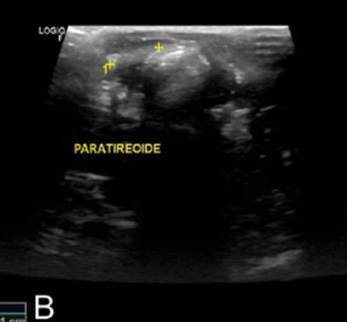

| | - ๋ถ๊ฐ์์ ๋น๋ |

- ํ ๊ฐ ๋น๋๊ฐ ๋๋ถ๋ถ. 2๊ฐ ๋น๋ : 10%, 3๊ฐ ์ด์ ๊ฑฐ์ ์์

- Percutaneous ultrasonography-guided ethanol ablation (with 96% ethanol)

- Percutaneous ultrasonography-guided radiofrequency heat ablation

- ์์ ์ ๋นํด ๋ ์ํ ์ ์์ผ๋, ์ ์ ํ ์กฐ์ง ๊ฒ์ฌ๋ฅผ ๋ณด๋ด์ adenoma, calcinoma, cycoplasma ๋ฑ ์กฐ์ง๋ณ๋ฆฌํ์ ํ๊ฐ๊ฐ ๊ฐ๋ฅํ ๊ฒ๊ณผ ๋ฌ๋ฆฌ ๊ทธ๋ฅ ์์ ๋ฒ๋ ค์ ํ๊ฐ x

- ์ผ๋ฐ์ ์ผ๋ก ์์ ๋ณด๋ค ์์ ๊ถ์ฅ